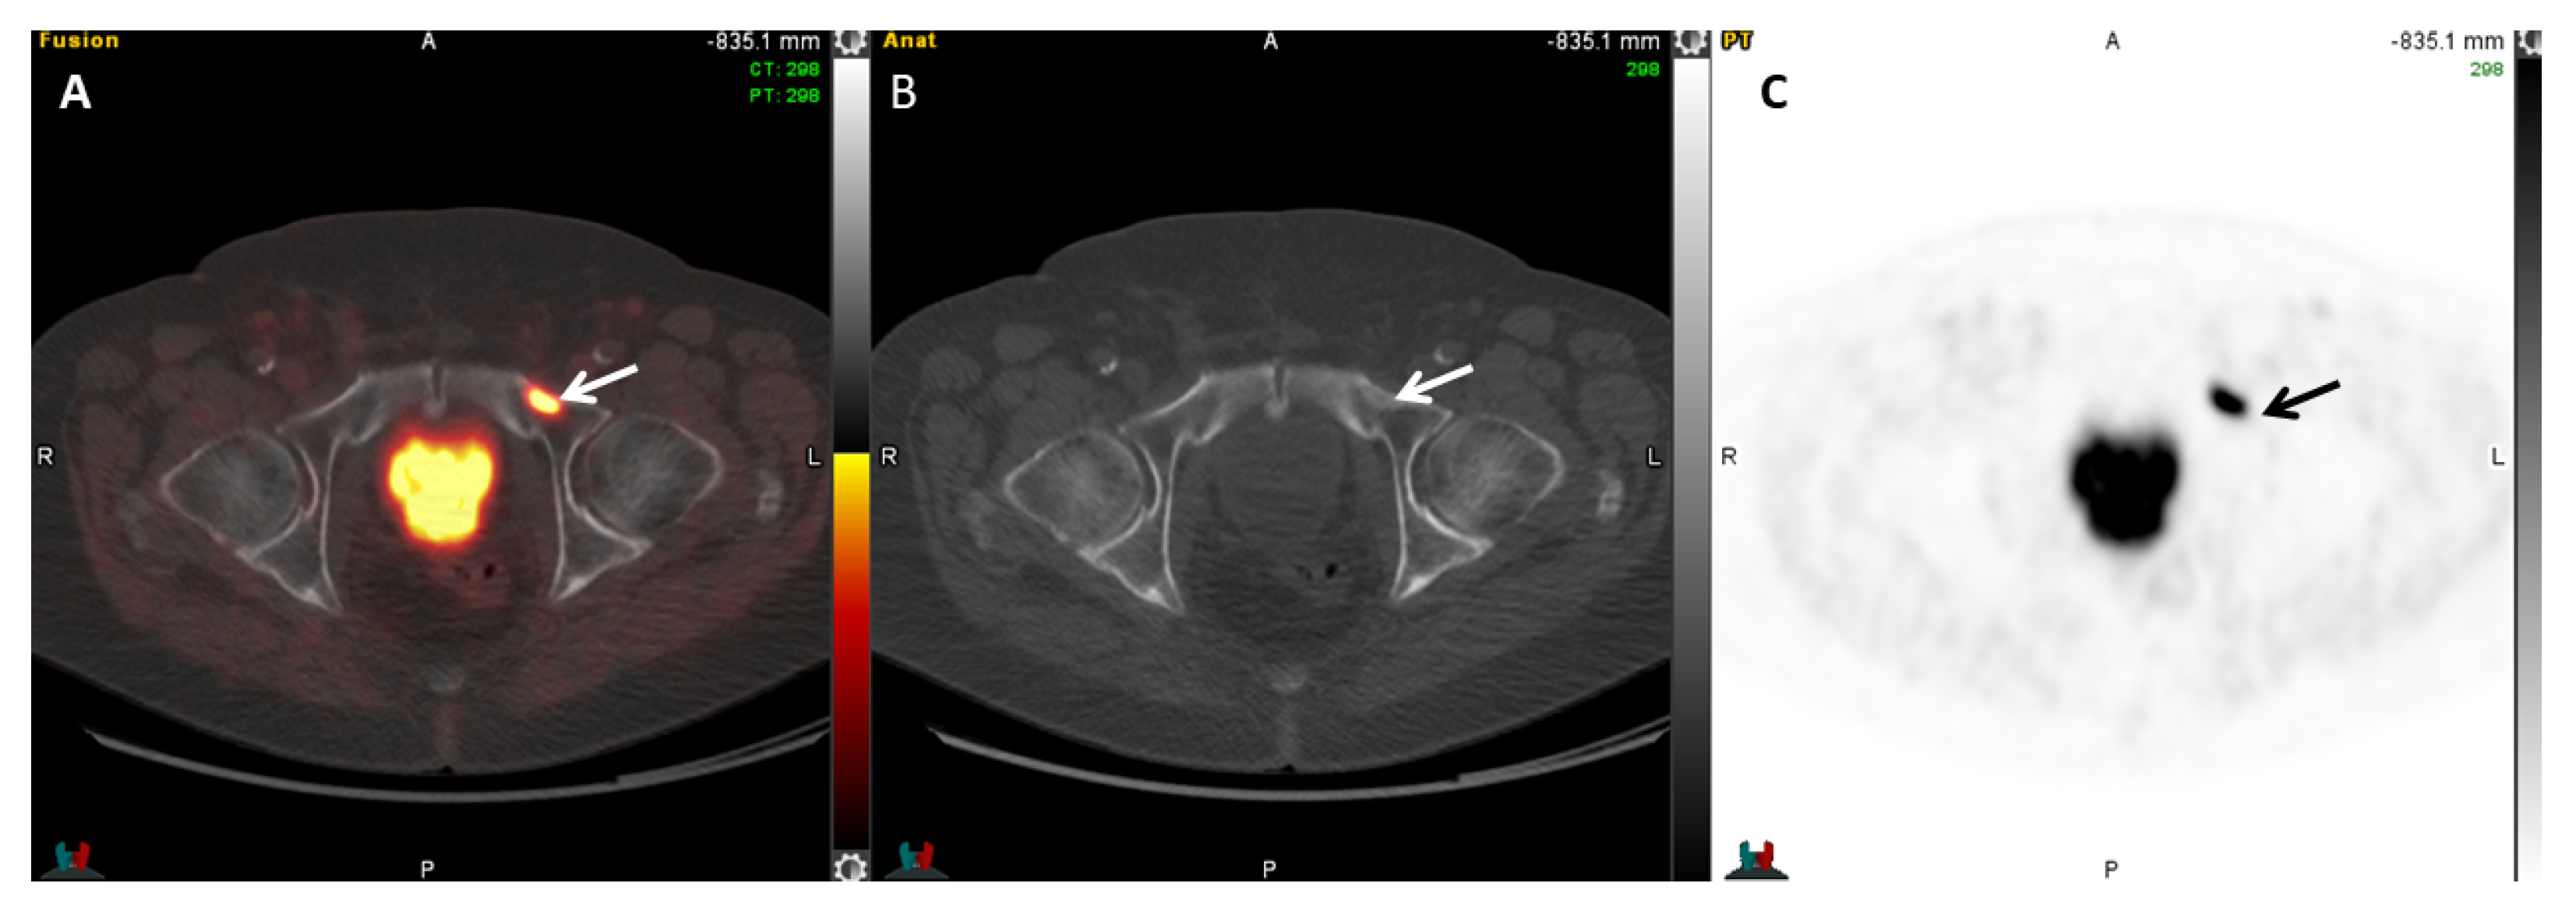

2.5.1. 68Ga-PSMA-11

- Rauscher, I.; Maurer, T.; Fendler, W.P.; Sommer, W.H.; Schwaiger, M.; Eiber, M. 68Ga-PSMA ligand PET/CT in patients with prostate cancer: How we review and report. Cancer Imaging 2016, 16, 14. [Google Scholar] [CrossRef]

- Hofman, M.S.; Hicks, R.J.; Maurer, T.; Eiber, M. Prostate-specific Membrane Antigen PET: Clinical Utility in Prostate Cancer, Normal Patterns, Pearls, and Pitfalls. Radiographics 2018, 38, 200–217. [Google Scholar] [CrossRef]

- Ceci, F.; Uprimny, C.; Nilica, B.; Geraldo, L.; Kendler, D.; Kroiss, A.; Bektic, J.; Horninger, W.; Lukas, P.; Decristoforo, C.; et al. 68Ga-PSMA PET/CT for restaging recurrent prostate cancer: Which factors are associated with PET/CT detection rate? Eur. J. Nucl. Med. Mol. Imaging 2015, 42, 1284–1294. [Google Scholar] [CrossRef]

- Perera, M.; Papa, N.; Christidis, D.; Wetherell, D.; Hofman, M.S.; Murphy, D.G.; Bolton, D.; Lawrentschuk, N. Sensitivity, Specificity, and Predictors of Positive 68Ga-Prostate-specific Membrane Antigen Positron Emission Tomography in Advanced Prostate Cancer: A Systematic Review and Meta-analysis. Eur. Urol. 2016, 70, 926–937. [Google Scholar] [CrossRef]

- Burgard, C.; Hoffmann, M.A.; Frei, M.; Buchholz, H.G.; Khreish, F.; Marlowe, R.J.; Schreckenberger, M.; Ezziddin, S.; Rosar, F. Detection Efficacy of 68Ga-PSMA-11 PET/CT in Biochemical Recurrence of Prostate Cancer with Very Low PSA Levels: A 7-Year, Two-Center “Real-World” Experience. Cancers 2023, 15, 1376. [Google Scholar] [CrossRef] [PubMed]